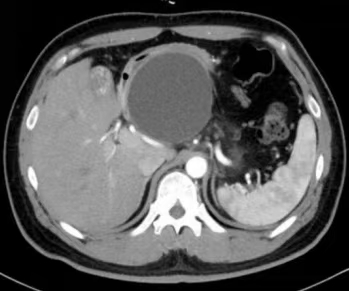

患者为36岁男性,1年前突发中上腹痛就诊当地医院,诊断为重症急性胰腺炎(胆源性、胰腺假性囊肿形成),病情多次复发。入院后行腹部CT提示胰头区可见较大类圆形低密度影,大小约8.9cm*7.3cm,考虑假性囊肿,胰尾渗出,胆囊增大伴瘀胆,邻近局部胰腺、胃腔、十二指肠、门静脉受压、变形等。

术前CT 显示胰头假性囊肿